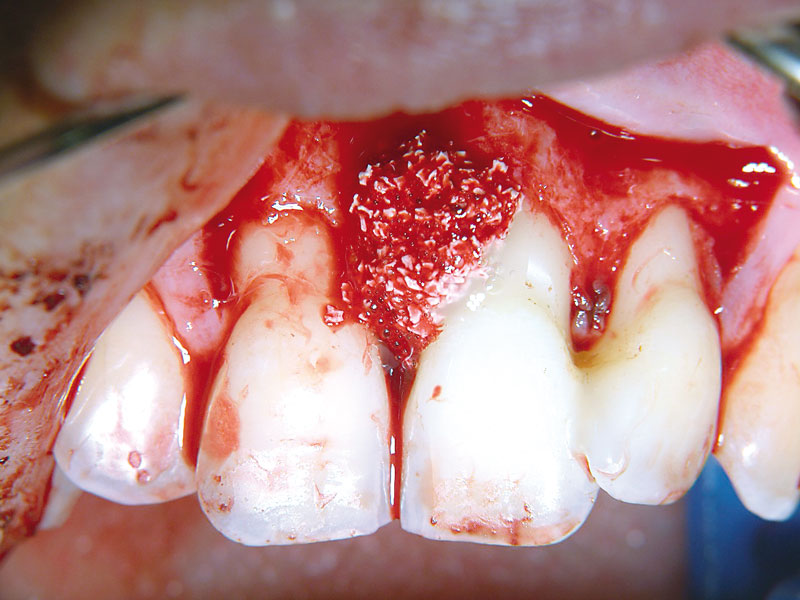

06/11 - Application of small cerabone® granules.Non-contained intrabony defect treated using cerabone®, collprotect® membrane and Straumann® Emdogain® - Dr. T. Schwaar (2)